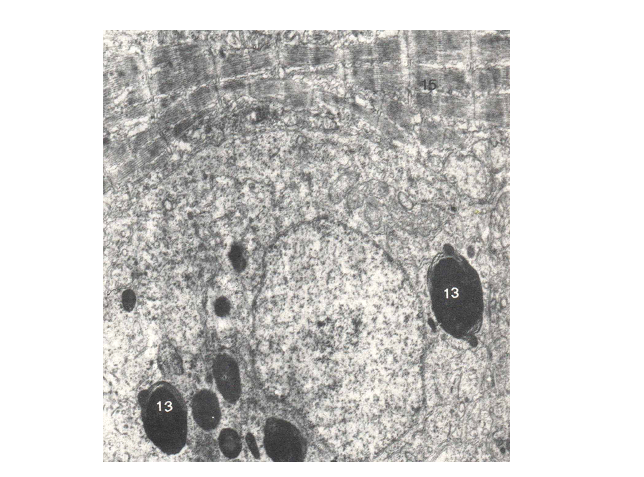

شکل 5:  نانوذرات آهن دز داخل اووسیت درون حبابها (13) حباب پینوسیتوزی(21). درشتنمائی x: 11200.

پخش میوفر در جنین در اعضاء مختلف متفاوت است و بخش اعظم آن در اندامهای خونساز ذخیره می گردد(11) (Forth,  et al). 8 روزپس از تزریق ، اندامکهای ذخیره ای حتی درسلولهای عضلانی و همراه (Satelleites ) جنین در حال رشد از نانوذرات میوفر انباشته شده اند (شکل5) بعد از 30 روز تغییری درمقدارذخایر نانوذرات آهن در اووسیت ها و تخمدان و اعضاء ماهی به چشم نمی خورد و فقط در جنین ذخیرۀ اندک آهن ادامه می یابد. این ذخایر در سلول های تخمدان بصورت واحد های مدور با تراکم متفاوت مشاهده می شوند. نانوذرات میوفر تقریبا بیشتر فضای سلولی را به شکل سیتو زومهای با اندازه های تقریبی 3/0 تا 7 میکرون پر می کند. در کبد قسمت اعظم فضای درونی سلول انباشته از میوفر است. تغییرات سیتولوژیکی در مادر بصورت کوتاه شدن میکروویلی ها در سلولهای کبدی وافزایش فضای بین سلولی مشاهده می شود(شکل5-7). سیستم رتیکولو اندوتلیال در طحال به مقدار قابل توجهی میوفر ذخیره می کند.(شکل7) .( 12،13) Granick1946, Greenberg1955 نشان دادند که آهن به محض ورود به سلول به آپوفریتین یک  ناقل آهن متصل می گردد. در جنین پس از 25 روزبزرگی ذخایر میوفر در مقایسه با تخمدان کمتر است(شکل 7). هپسیدین یک پپتید 25 اسید آمینهای که در کبد سنتز می شود نقش تعیین کننده ای در متابولیسم آهن دارد.  مقدار کم هپسیدین یک عامل مهم انباشتگی آهن در بدن یا بروز اختلاتلات ایمنی مخصوصا در بیماری های کبدی می باشد(14،15 )(Thomas et al2005، Nemett et al.2004)